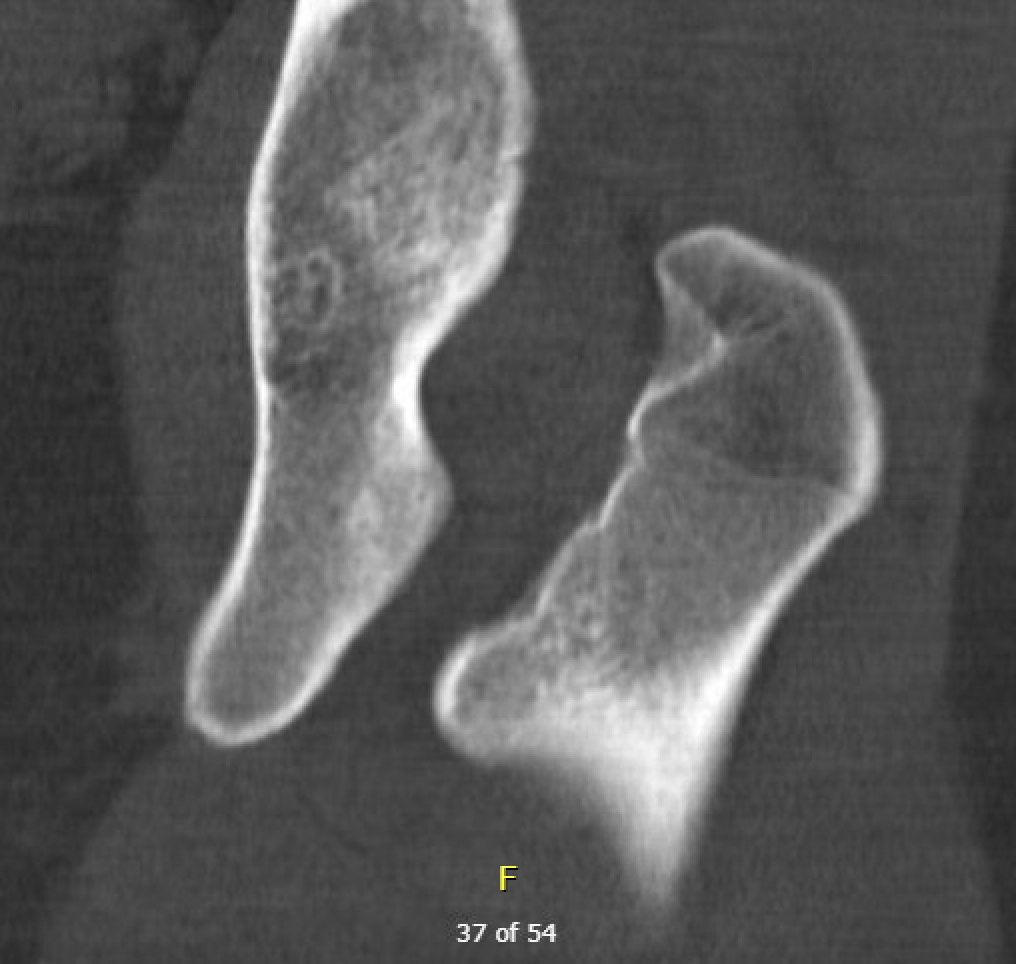

Definition

Narrowing of the ischiofemoral space between lateral ischium and lesser trochanter

Entrapment / compression of quadratus femoris

Reduced ischiofemoral space - distance between the lesser trochanter and the ischial tuberosity

Reduced quadratus femoris space - distance between hamstring tendon and iliopsoas

Inflammation / edema in quadratus femoris +/- fatty degeneration

CT